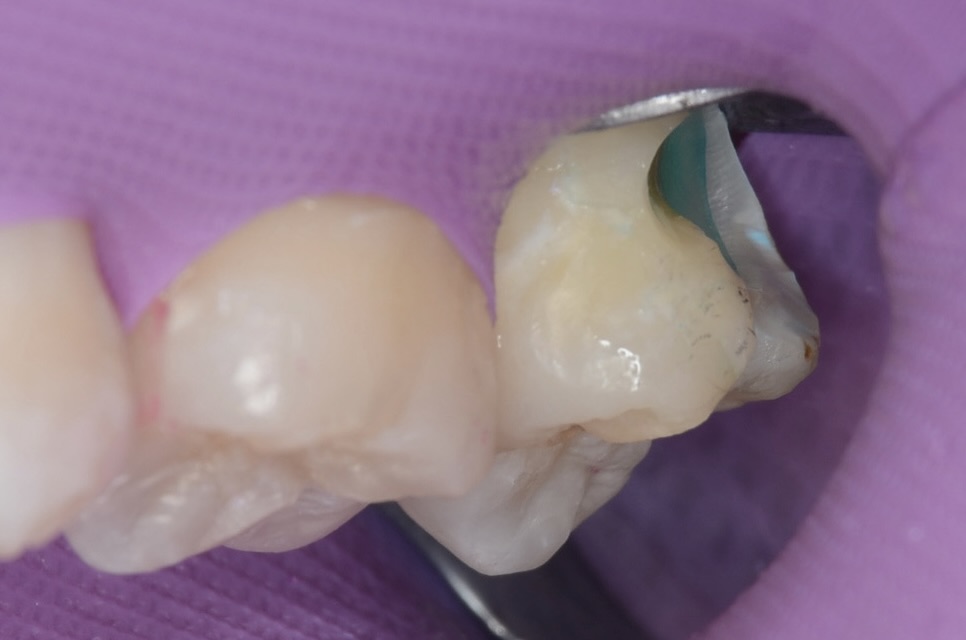

上顎7番頬側面観

歯ブラシがしにくい上の奥歯の横は、虫歯ができやすい場所でもあります。 -

かつてレジンで治療されている部分が虫歯になっています。 -

ラバーダム装着